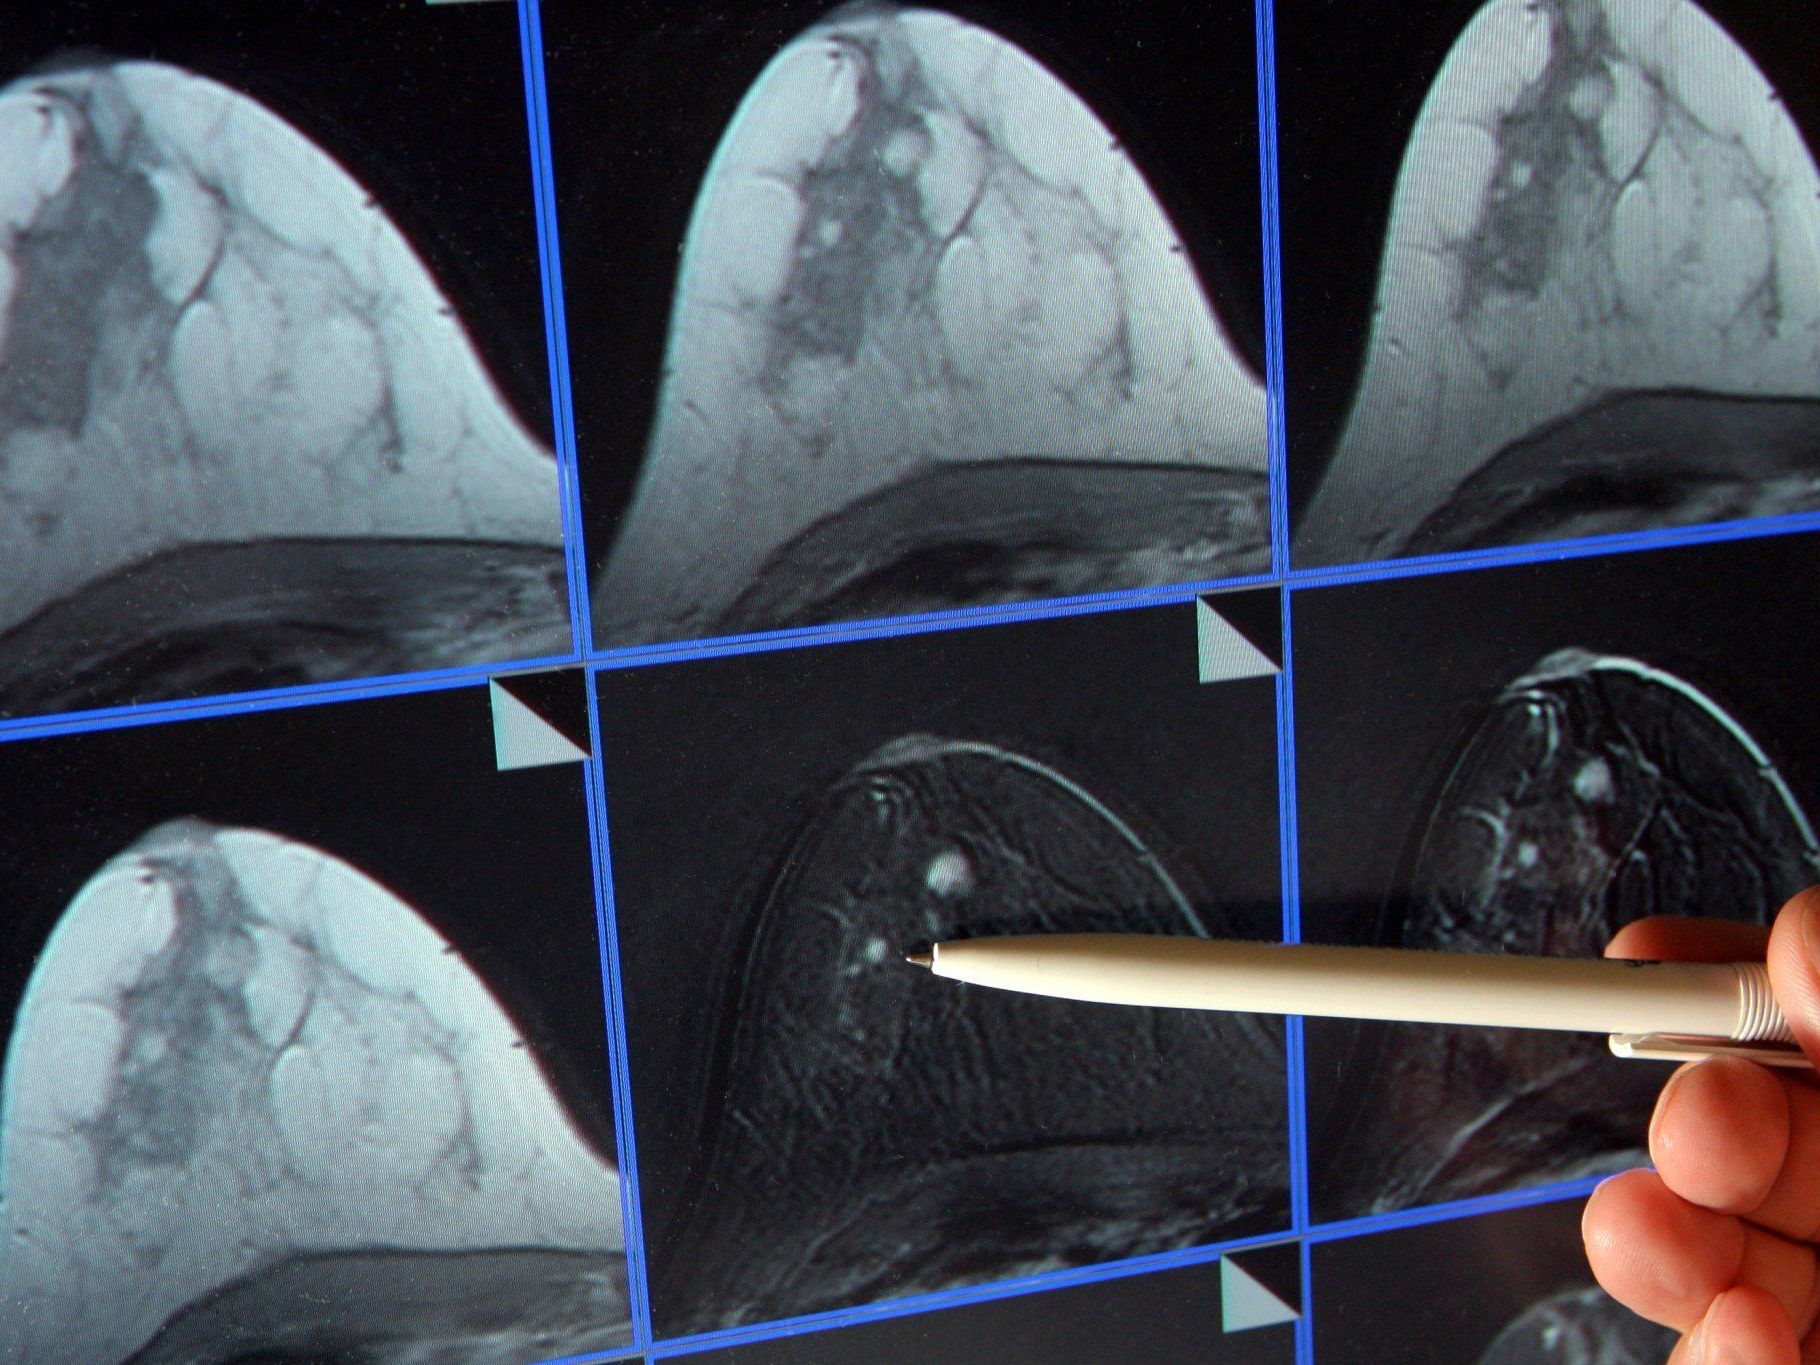

Man schätzt, dass bisher in Österreich bis zum Start des neuen Programms, es wurde seit Jahren von Fachleuten gefordert, etwa 45 Prozent der Frauen zur Vorsorge-Mammografie wegen Brustkrebs gingen. In Österreich gibt es jedes Jahr rund 5.000 Neuerkrankungen, 1.600 Frauen sterben jährlich an einem Mammakarzinom. Eine Beteiligung von 70 Prozent sollte die Sterberate um rund 30 Prozent senken.

Dabei sollte das organisierte Mammografie-Screeningprogramm gerade Frauen zu der Untersuchung bringen, die bisher noch nicht teilnahmen. Doch gerade das ist bisher ausgeblieben. An den Zahlen kann es keinen Zweifel geben, da mit der Etablierung des bundesweiten Programms alle Untersuchungen genau dokumentiert werden müssen.